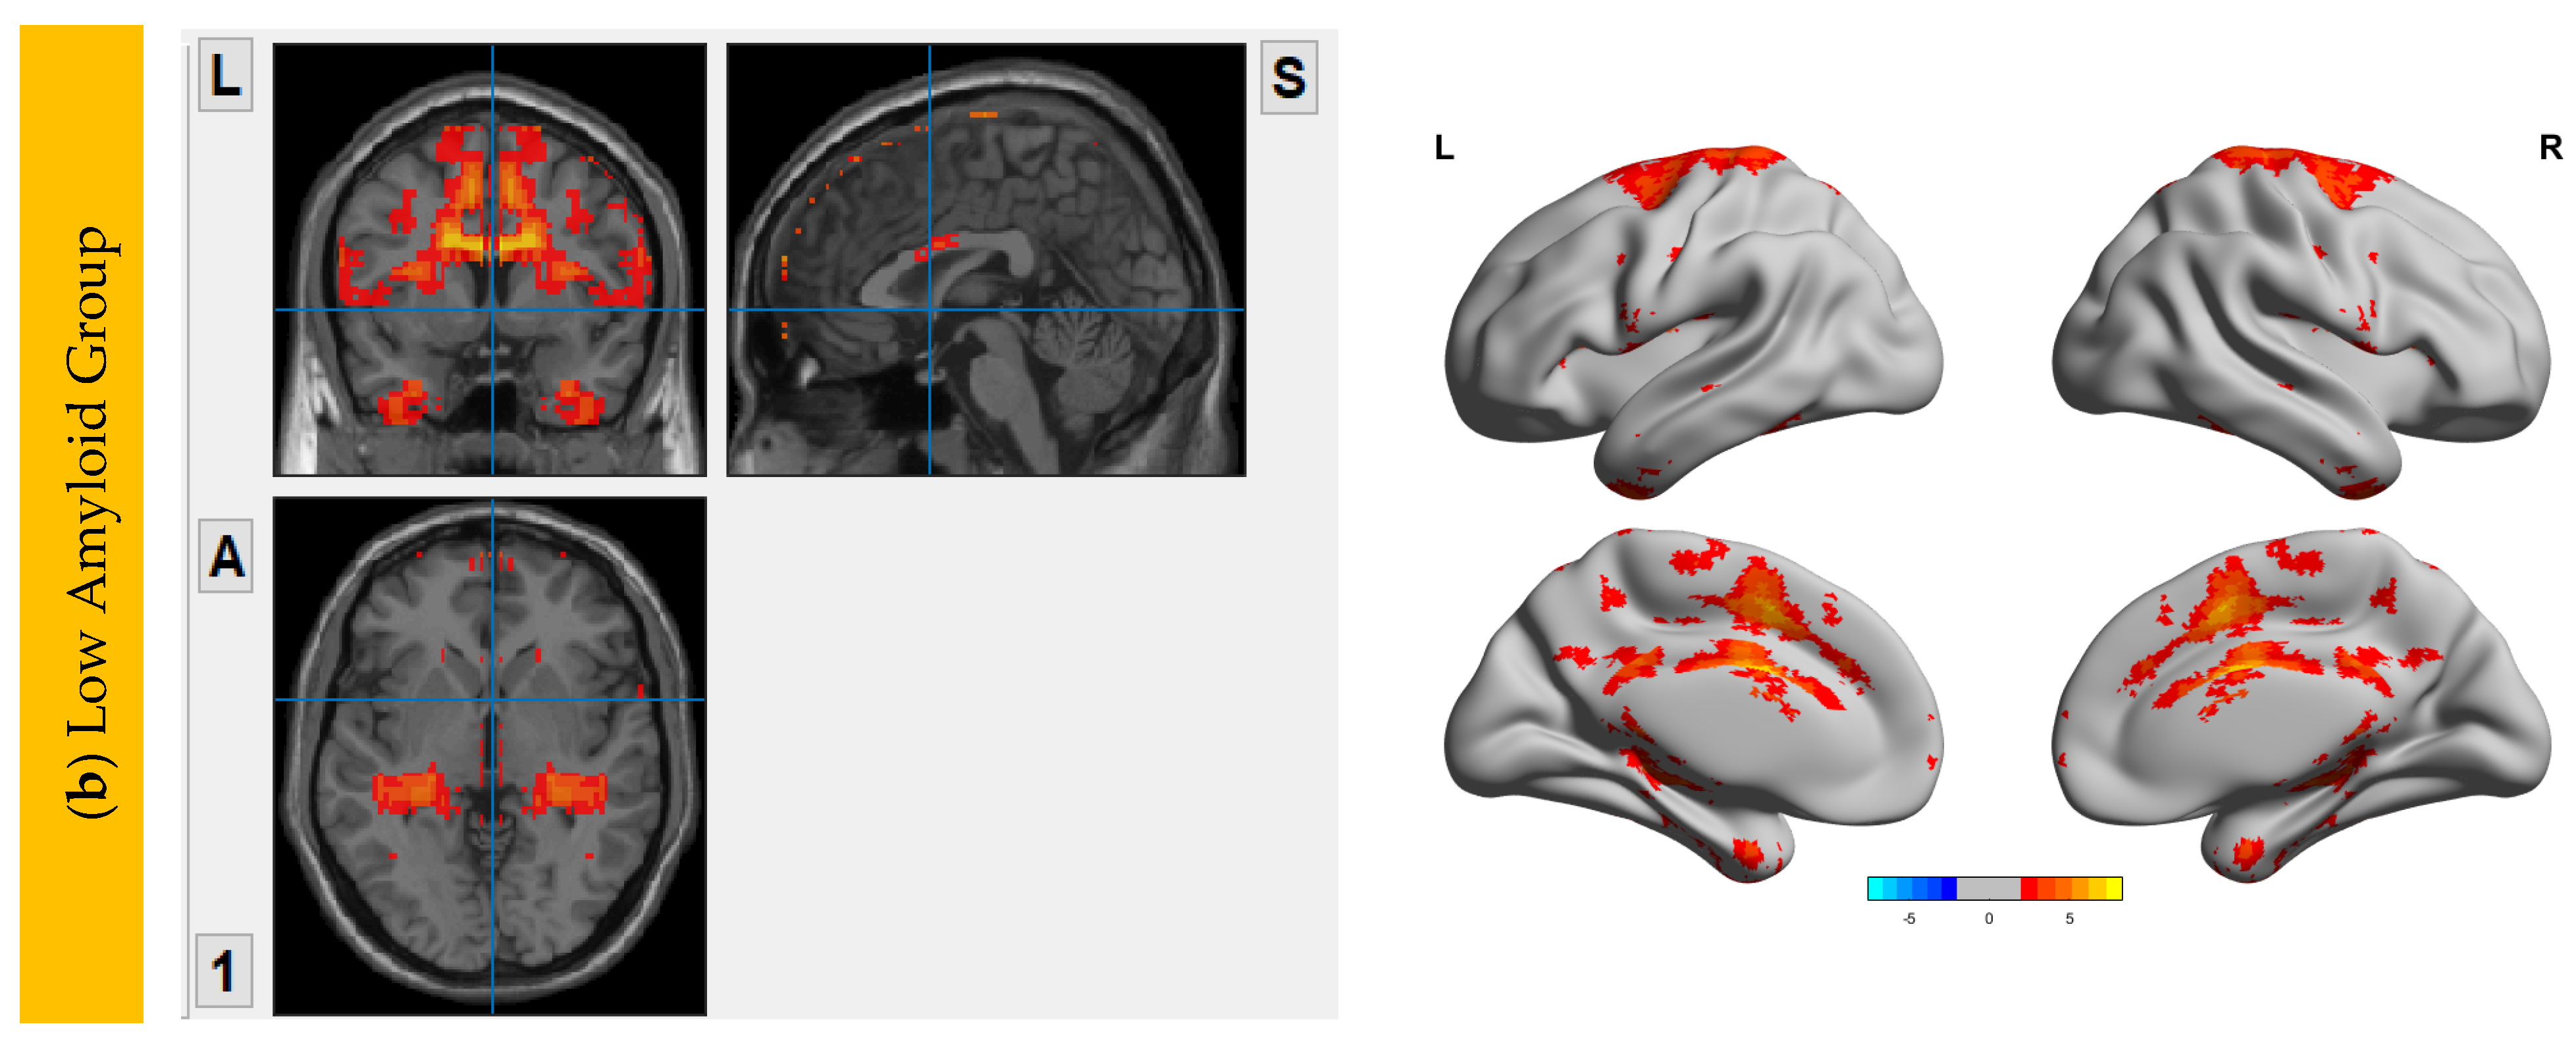

6.3. Interhemispheric Functional Connectivity (VMHC) Maps

7. Correlation Analysis between Aβ Accumulation and IFC

7.1. Within DMN

7.2. Within CEN

7.3. Within SN

7.4. Within SRN

7.5. Within SMN